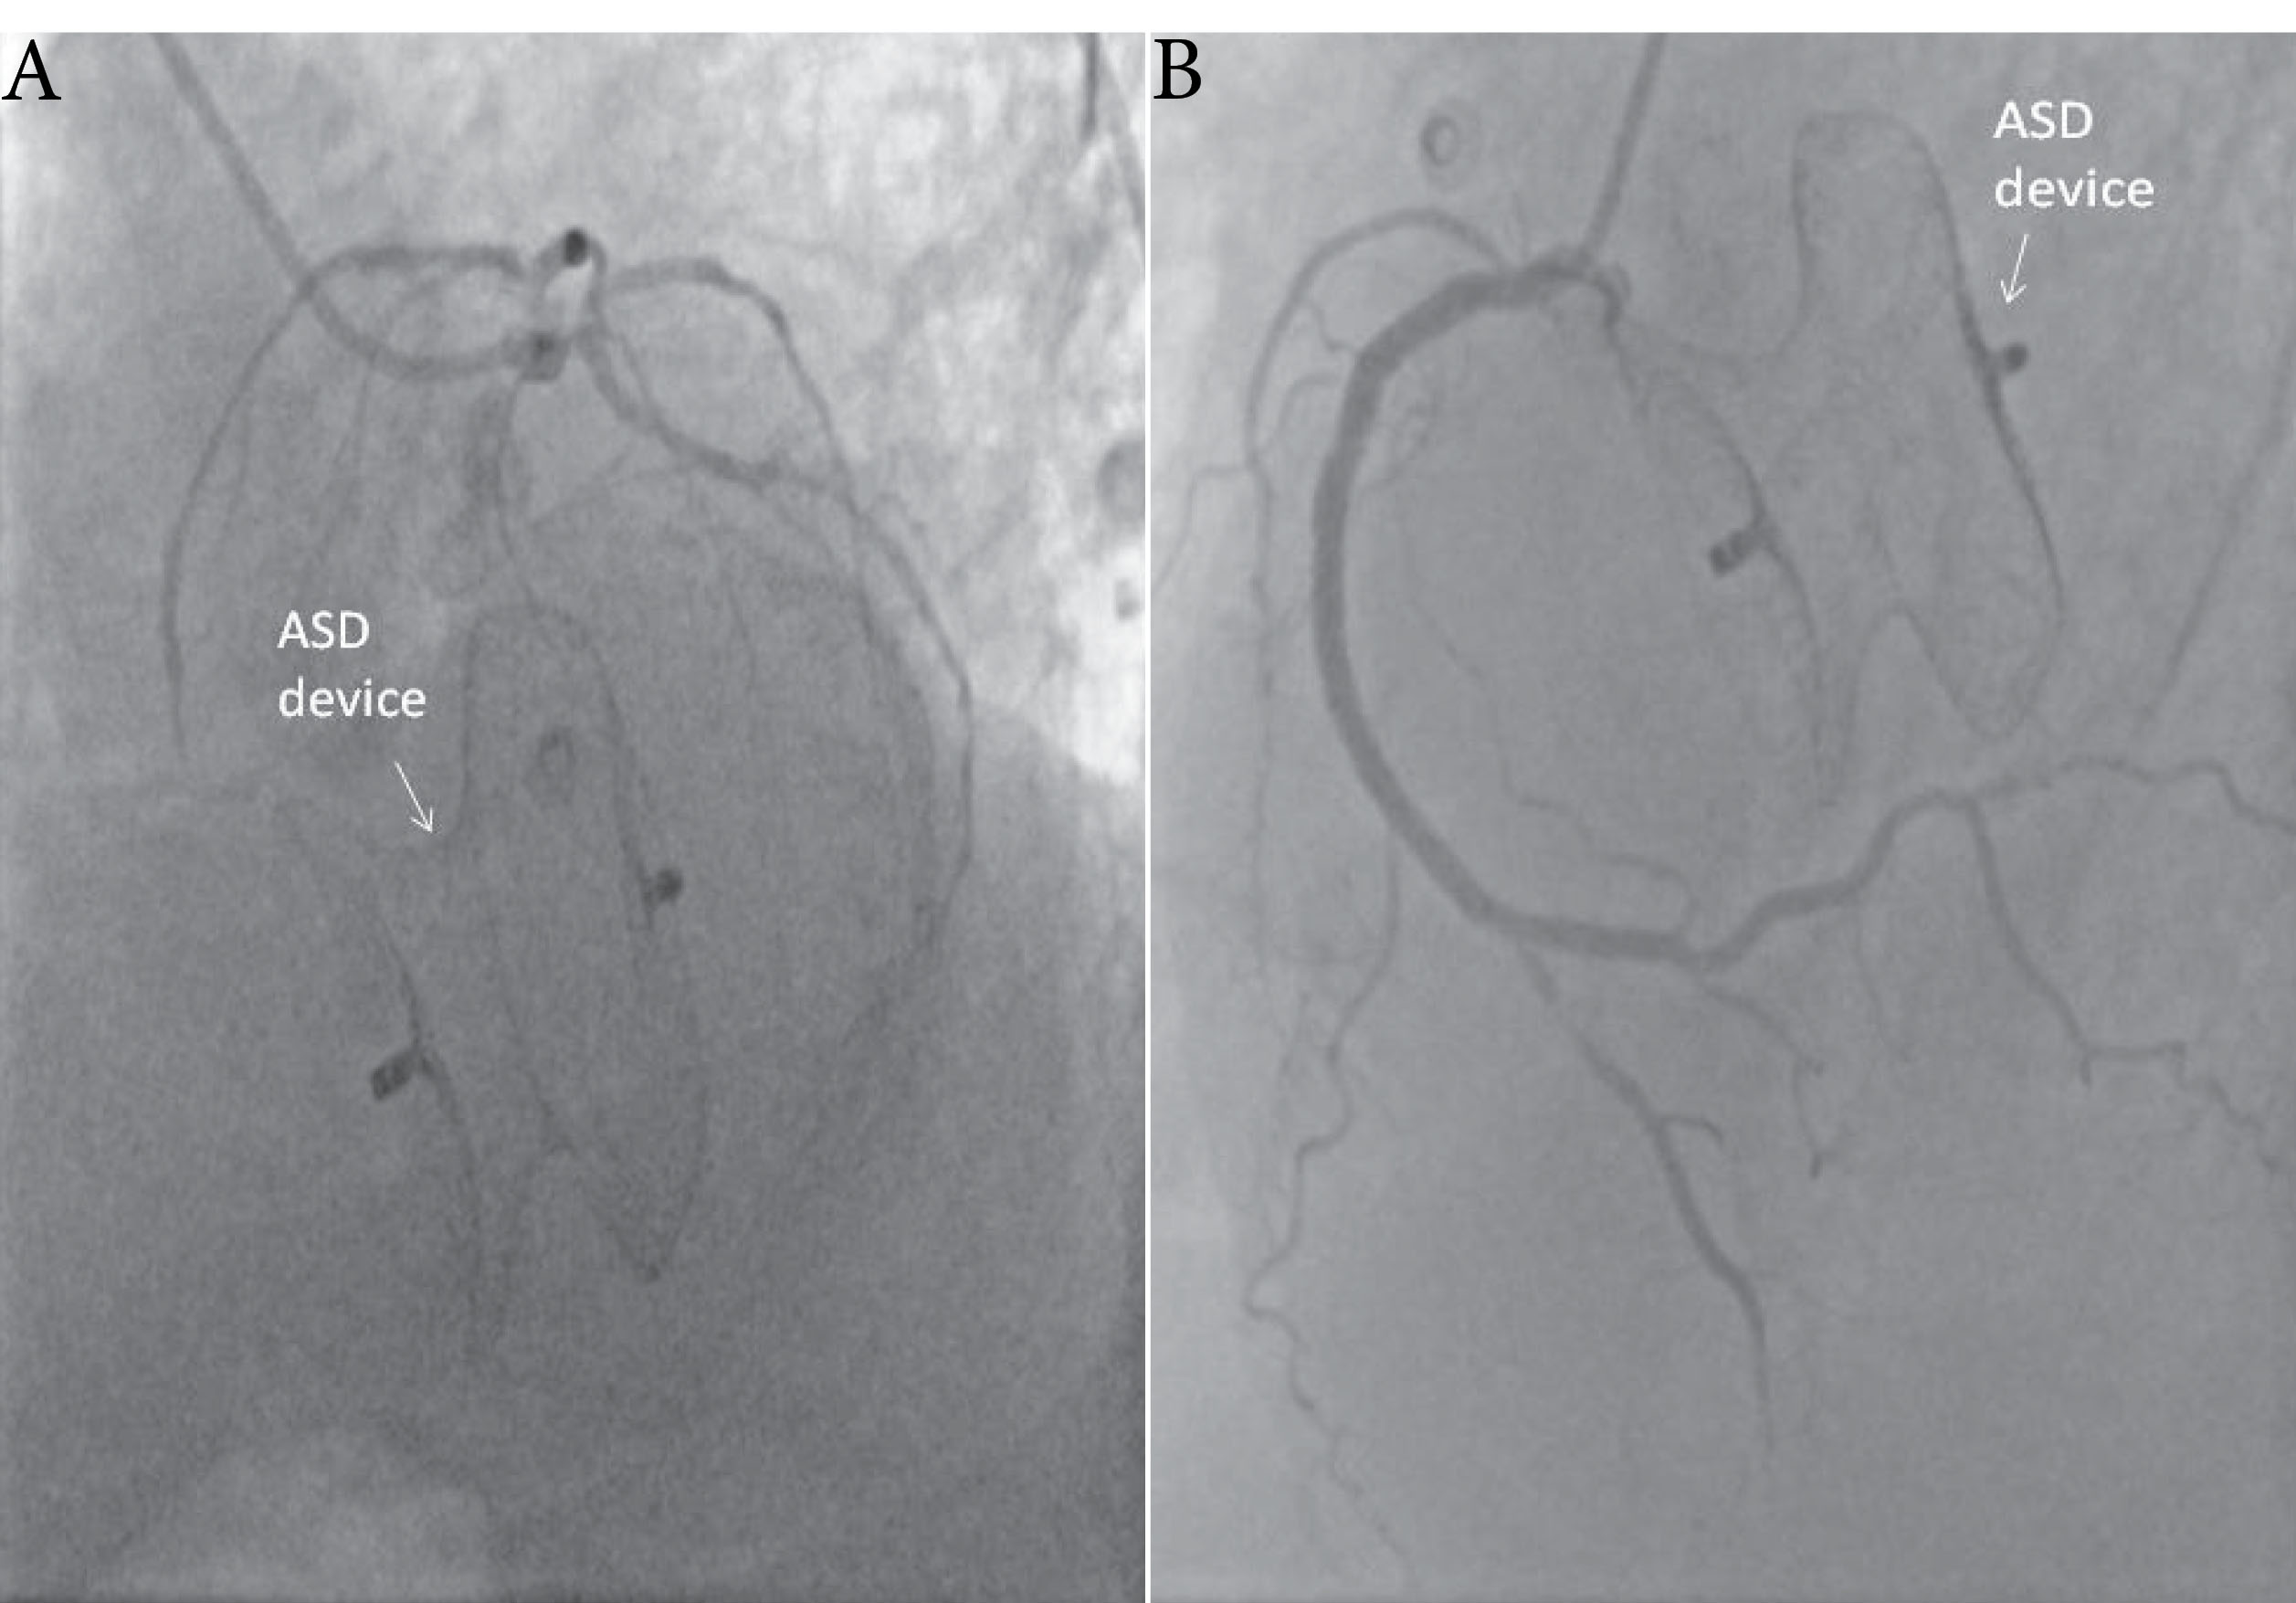

A 56-year-old male patient presented with chest pain and progressive dyspnea for one year. The patient’s history revealed a percutaneous intervention with device closure of ASD seven years ago and acute inferior MI one year ago. He did not have any medical report about previous echocardiographic examinations. Physical examination on admission revealed a grade 4/6 apical systolic murmur, radiating to the axilla. His electrocardiography showed sinus tachycardia at 110 beats/min. The patient underwent transthoracic echocardiography and transesophageal echocardiography (TEE), documenting the presence of severe functional MR (regurgitant volume:61 ml, effective regurgitant orifice area: 0,4 cm2) with tethering at posterior leaflet related to basal and mid inferior wall akinesia and anterior leaflet compression related to device with reduced ejection fraction (EF 34 %) (). The ASD device position and size were problematical in both two-dimensional (2D) and three-dimensional (3D) echocardiographic examination (). The device was oversized, malposed and the margin of the device compressed the mitral anterior leaflet and posteromedial commissure (). No shunt or perforation was detectable. A relative mitral stenosis (mean gradient 9 mmhg) releated to compression of mitral valve was observed. Coronary angiography showed two-vessel disease and ASD closure device malposition (). The patient underwent surgical operation. Surgical inspection revealed that the device was intact but stuck to the septum and hardly seperated. It was oversized, malposed and ischemic macroscopic changes in both leaflet (more prominently in the posterior) was observed (). No perforation also was observed in surgery. Following device removal, ASD closure with an autologous pericardial patch, mitral valve replacement combined with coronary artery bypass graft surgery were performed.

Figure 2. Left (A) and right (B) coronary angiogram showing oversized ASD occluder device. ASD, Atrial septal defect